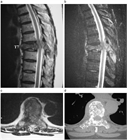

1. がんの既往のある患者が脊椎に痛みを訴えた場合、転移性脊椎腫瘍を念頭に置くことが推奨される(推奨度1)

1. 転移性脊椎腫瘍を疑った場合、全身の造影CTを撮影することが推奨される(推奨度1)